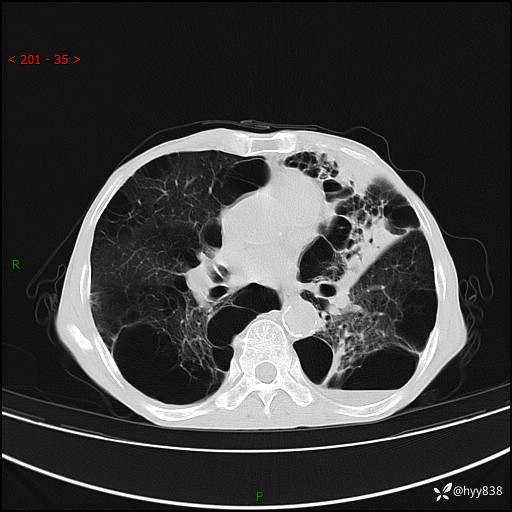

胸部CT平扫+增强